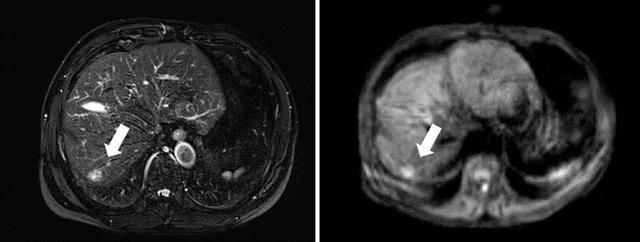

(▲腹部增强MRI上T2WI和DWI序列提供诊断肝癌更多的图像信息)